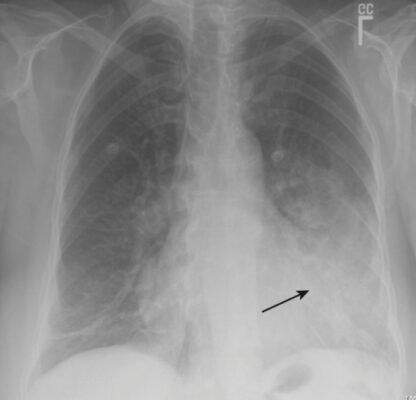

- Bởi vì các phân thuỳ phổi không gắn với các rãnh liên thuỳ, tất cả các bờ của viêm phổi phân thuỳ có xu hướng như bông (fluffy) và không rõ ràng (Hình 4).

- Không giống như viêm phổi thùy, viêm phế quản phổi phân thuỳ tạo ra dịch tiết lấp đầy phế quản. Do đó thường không có hình ảnh phế quản chứa khí và thường có giảm thể tích (xẹp phổi) phối hợp với viêm phế quản phổi.